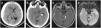

A 60-year-old woman, with past medical history of stroke (under treatment with aspirin and clopidogrel) presented with headache and incomplete palsy of III right cranial nerve. The patient referred a minor head trauma some days ago. Brain computed tomography (CT) showed an extended right-sided subdural haematoma (14mm), with mass effect, and midline shifted to the left (10mm) (Fig. 1). A craniotomy and evacuation of the subdural collection was done. The patient awaked confused, with right-sided hemiparesis. Cervical spine pathology and stroke were excluded. Magnetic Resonance Image (MRI) of the brain showed changes in the contralateral cerebral peduncle, compatible with Kernohan–Woltman notch phenomenon. She was transferred to the general ward with moderate right-sided hemiparesis.

Brain CT showed extended right-sided subdural haematoma (A), with compression of left cerebral peduncle against free tentorial (B, white arrow). Brain MRI reveals a rounded hyperintense T2 FLAIR (C) and DW1 (D) images in left cerebral peduncle (white arrow), at 2 days after initial injury.